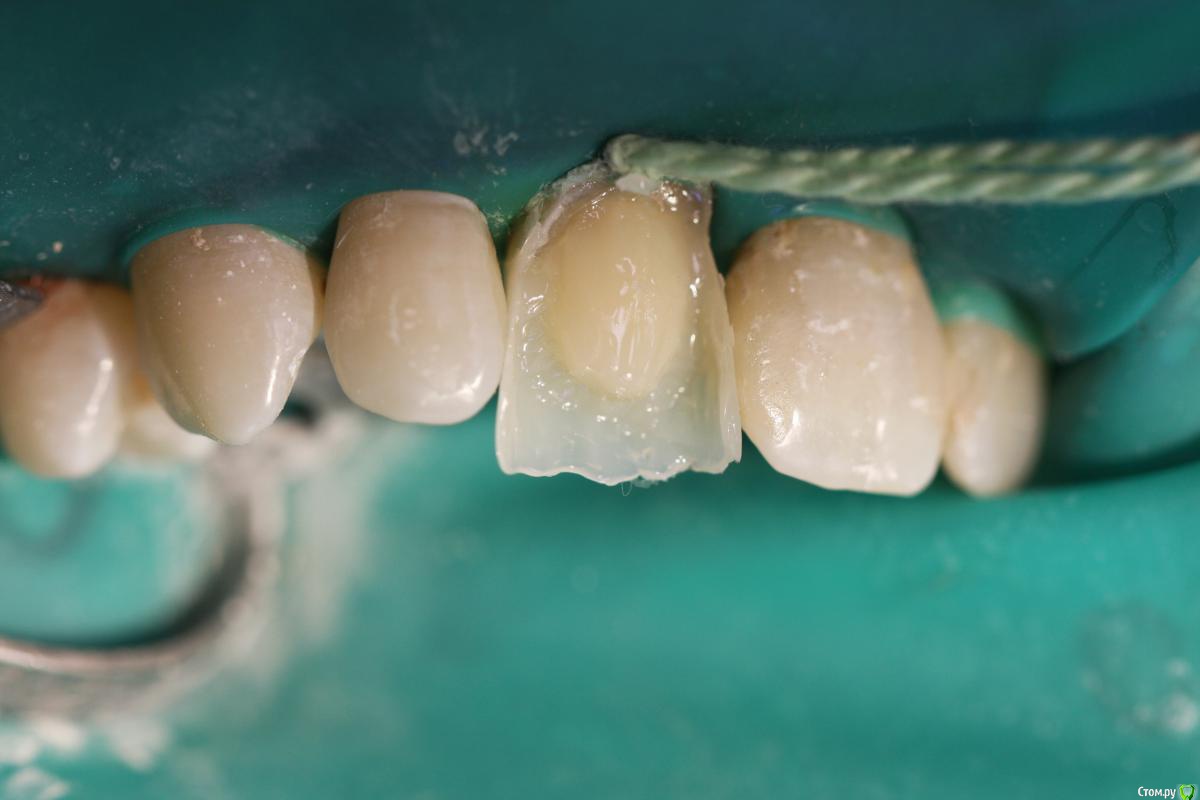

skeettrap Опубликовано 19 марта, 2016 Поделиться Опубликовано 19 марта, 2016 Работа из категории - для души. Попутно сделан кариес у 12 с медиальной стенки , 21 - только подполирована медиальная стенка. 3 Ссылка на комментарий

Мартовский Опубликовано 19 марта, 2016 Поделиться Опубликовано 19 марта, 2016 С таким феррулом быстро сломает. Если уж идти на прямую реставрацию, то штифт надо гораздо толще брать, и пояс прочности нужен более выраженный. Про "дешевле" согласен, про "эстетичнее" промолчу 7 Ссылка на комментарий

horreodor Опубликовано 19 марта, 2016 Поделиться Опубликовано 19 марта, 2016 не плохо получилось... да и стоять я думаю нормально будет, если пиво не открывать зубами... Ссылка на комментарий

St. Опубликовано 20 марта, 2016 Поделиться Опубликовано 20 марта, 2016 Зуб красивый получился, главное чтоб не сломала. Ссылка на комментарий

skeettrap Опубликовано 22 марта, 2016 Автор Поделиться Опубликовано 22 марта, 2016 У Вас хорошо получилось, каким материалом восстанавливали? Только не поняла, почему сразу кламп не надели?удобнее было бы, имхо.Спасибо. Материал Filtek Supreme. Без клампа удобнее восстанавливать контактные и небную стенки, а с ним удобнее пришейку. Ссылка на комментарий